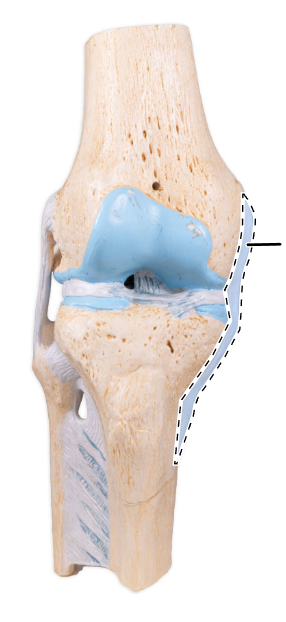

What is the joint shown here?

The tibiofemoral joint.

What is the joint shown here?

The tibiofemoral joint.

What ligament is shown here?

Medial (tibial) collateral ligament.

What ligament is shown here?

Medial (tibial) collateral ligament.